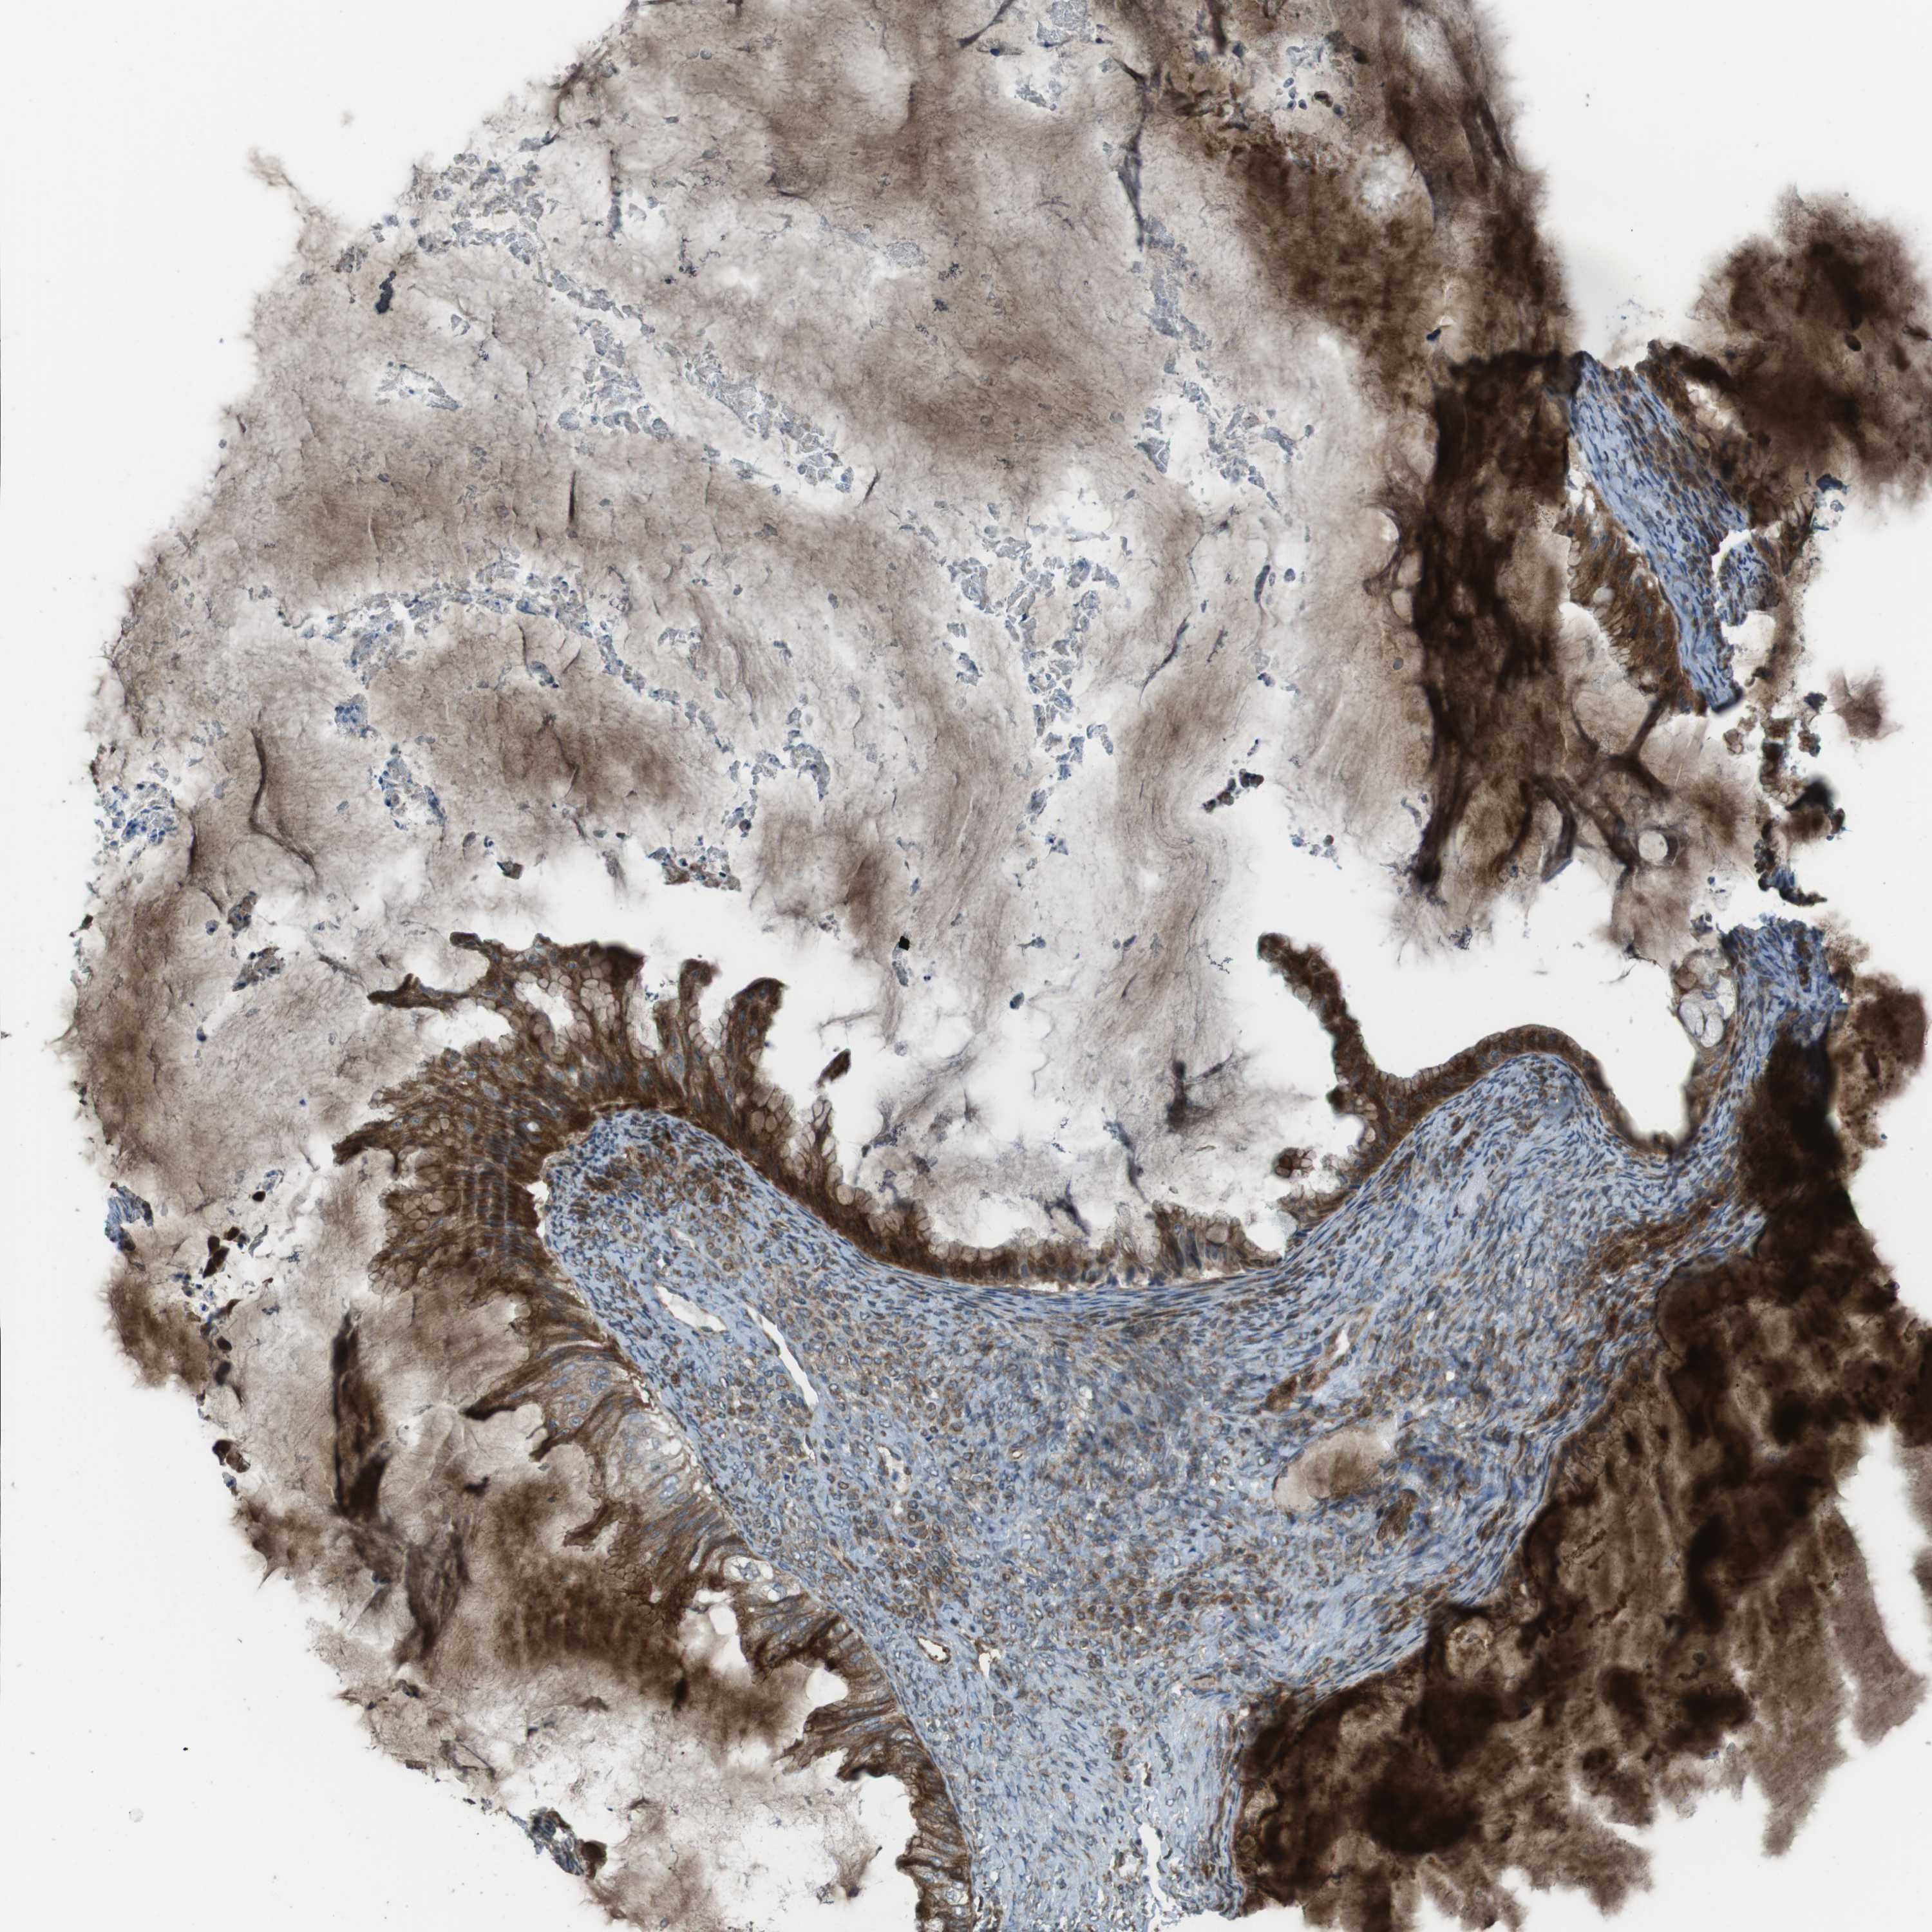

OVARIAN CANCER - Protein expressioni

A mouse-over function shows sample information and annotation data. Click on an image to view it in a full screen mode. Samples can be filtered based on level of antibody staining by selecting one or several of the following categories: high, medium, low and not detected. The assay and annotation is described here.

Note that samples used for immunohistochemistry by the Human Protein Atlas do not correspond to samples in the TCGA dataset.

Antibody stainingi

Antibody staining in the annotated cell types in the current human tissue is reported as not detected, low, medium, or high, based on conventional immunohistochemistry profiling in selected tissues. This score is based on the combination of the staining intensity and fraction of stained cells.

Each image is clickable and will lead to virtual microscopy that enables deeper exploration of all samples and also displays staining intensity scores, fraction scores and subcellular localization as well as patient and tissue information for each sample.

Antibody HPA015705

Staining

High

Medium

Low

Not detected

Intensity

Strong

Moderate

Weak

Negative

Quantity

>75%

75%-25%

<25%

None

Location

Nuclear

Cytoplasmic/membranous

Cytoplasmic/membranous,nuclear

Cystadenocarcinoma, serous, NOS

Carcinoma, endometroid

Cystadenocarcinoma, mucinous, NOS

Carcinoma, NOS